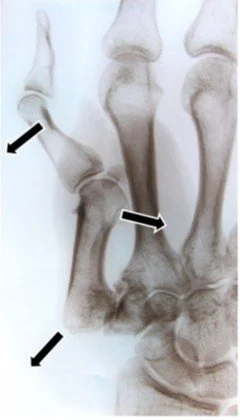

Common Operations